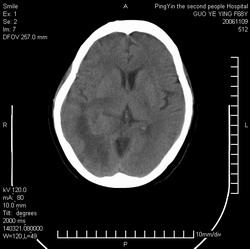

郭*,61岁 ,头痛半月并有复视

右侧颞枕叶见形态不规则等密度灶,灶周可见水肿灶,考虑:1、胶质瘤?2、转移瘤?建议做增强或mri检查

右侧颞枕叶见形态不规则等密度灶,中心见低密度影,灶周可见水肿明显,右侧脑室受压变窄,考虑胶质瘤或转移瘤。请作增强或mri检查

平扫观察右侧至少有3个结节伴周围水肿,首先考虑转移。先查肺部吧。

右侧颞枕叶示结节状影,外缘示片状低密度影,相应脑室未见明显受压,考虑转移瘤。

右侧脑实质内多发结节影并指状水肿.

意见:考虑多发转移瘤.

右侧颞枕叶见多个形态不规则等密度灶,中心见低密度影,灶周可见水肿明显,右侧脑室受压变窄,考虑转移瘤或胶质瘤。请作增强或mri检查